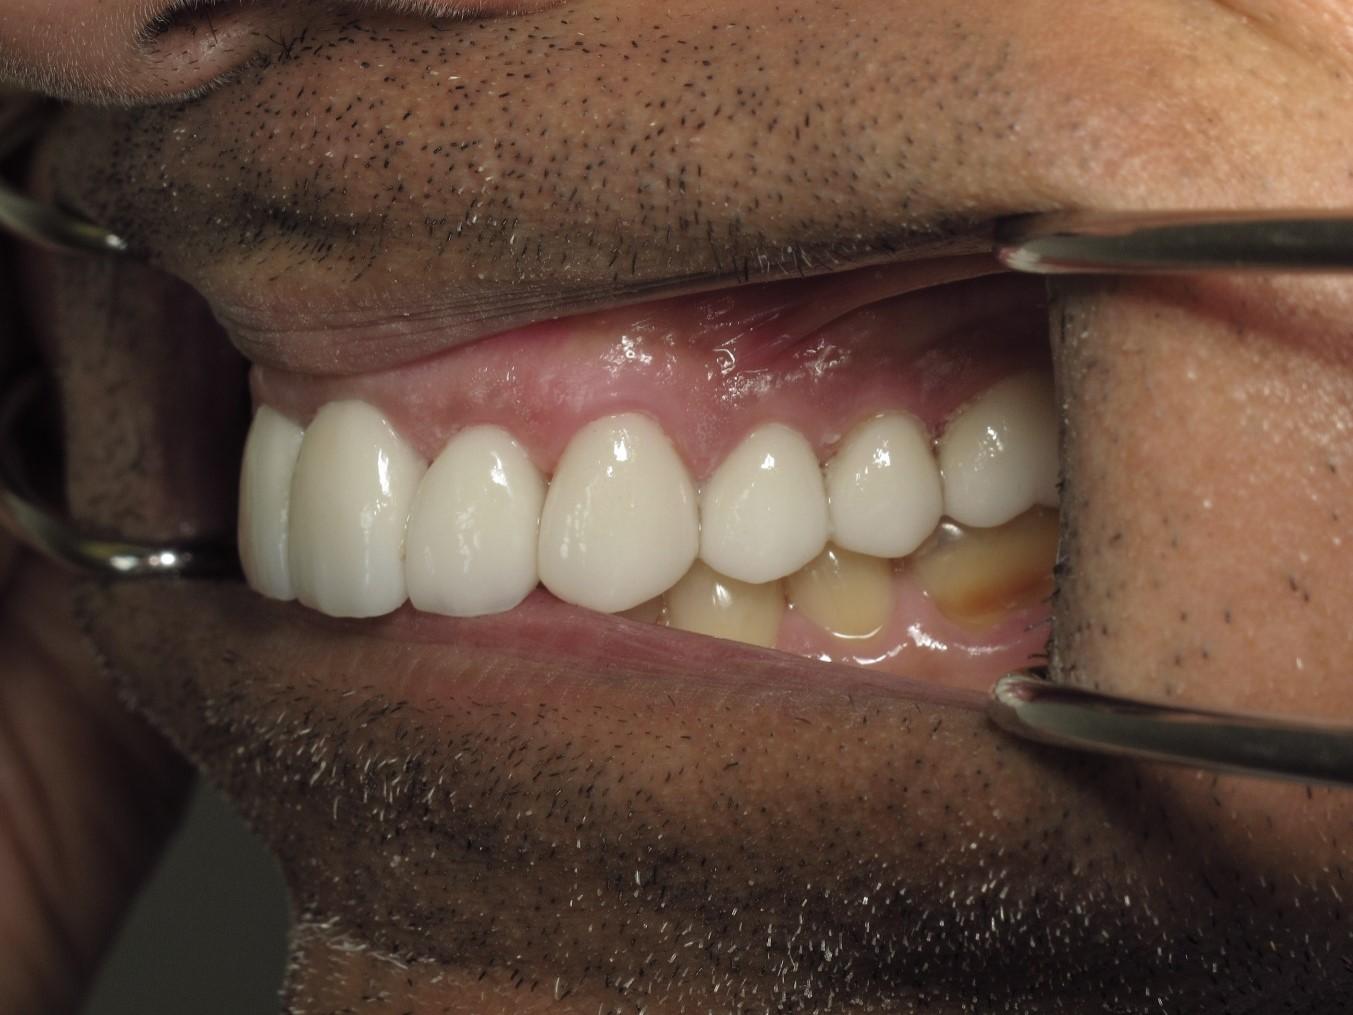

https://demo.discussdentistry.com/forums/topic/no-prep-veneers/#post-26022 <![CDATA[No prep veneers]]> https://demo.discussdentistry.com/forums/topic/no-prep-veneers/#post-26022 Mon, 15 Apr 2024 03:43:21 +0000 Amit Kumar The patient is a successful physician who desired an improved smile but did not want to “shave down” his teeth.

No prep veneers were delivered from the upper second bi-cuspid to the second bi-cuspid on the contra-lateral side.  No temporaries were needed.

The patient also wanted to include his lower anterior teeth, however,Pre opPre op right sidePre op left sideTry in right sideTry in left sideFinal 1Final 2 there was not enough clearance to accomplish this using no-prep technique.

You can note that the upper central was lengthened by 20%.